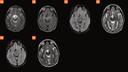

Case 1

10-year-old female with severe traumatic brain injury. Top row GOBrain (2A–D: Sagittal T1w, axial T2 TSE, axial T2 FSE FLAIR, and axial T2*) obtained 3 days after the conventional MRI. Bottom row, routine sequences (2E–H: Sagittal T1w, axial T2w, axial FLAIR, and susceptibility-weighted imaging (SWI)). Findings consistent with brain contusion in the posterior parieto-occipital cerebral hemispheres and subdural bleed along the left tentorium (arrow). There is comparable conspicuity of the contusion and blood products with the routine and the GOBrain-5-minute protocol.